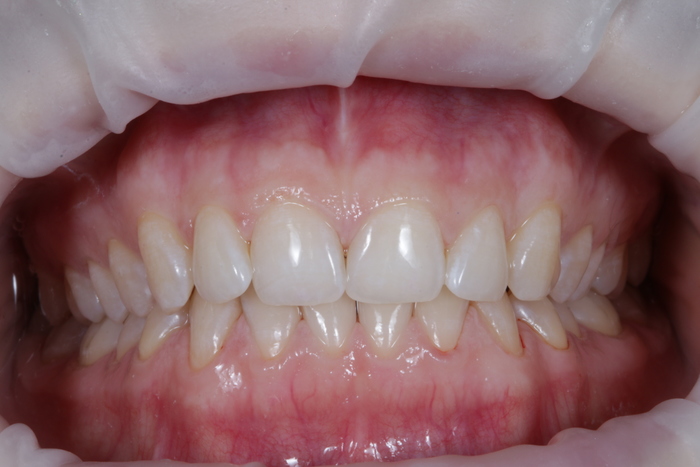

И вот картинка спустя полгода «ношения» новой временной коронки:

Я согласен, что эстетика хромает. Давно пора менять временную коронку на постоянную, что улучшит результат. Но, как я говорил, все упирается в финансы.

С другой стороны… с этого мы начали:

а на этом остановились: